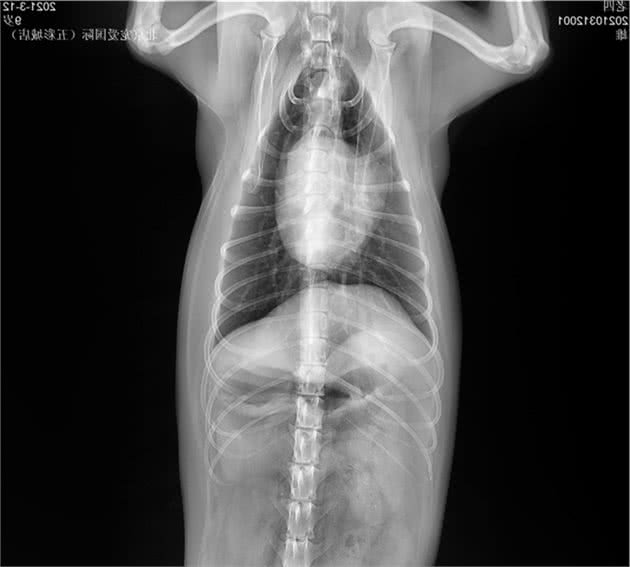

临床检查:TPR正常,精神沉郁,步态缓慢,肛门左侧有一大的鼓包,较软;直肠检查肛周左侧有一疝孔。

x线检查

会阴疝